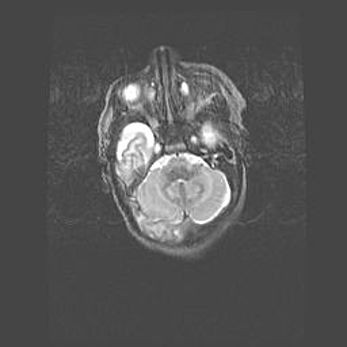

Лейкомаляция с кистозно-глиозной дегенерацией головного мозга.

Возраст: 2 месяца 25 дней

Вес: 6400 г

Окружность головы: 40 см

Срок гестации: 41 неделя

Лейкомаляцию относят к ишемически-гипоксическим повреждениям головного мозга, диагностируемым у новорожденных. При лейкомаляции в головном мозге обнаруживают очаги некроза, возникшие после тяжелой гипоксии и нарушения кровотока. В процессе морфогенеза очаги проходят три стадии: 1) развития некроза, 2) резорбции и 3) формирования глиозного рубца или кисты. Перивентрикулярная лейкомаляция (ПЛ) встречается примерно в 12% случаев среди новорожденных, обычно – у недоношенных детей, причем, частота ее зависит от массы, с которой младенец появился на свет. Наибольшее число малышей страдает лейкомаляцией, если масса при рождении 1500-2500 г.